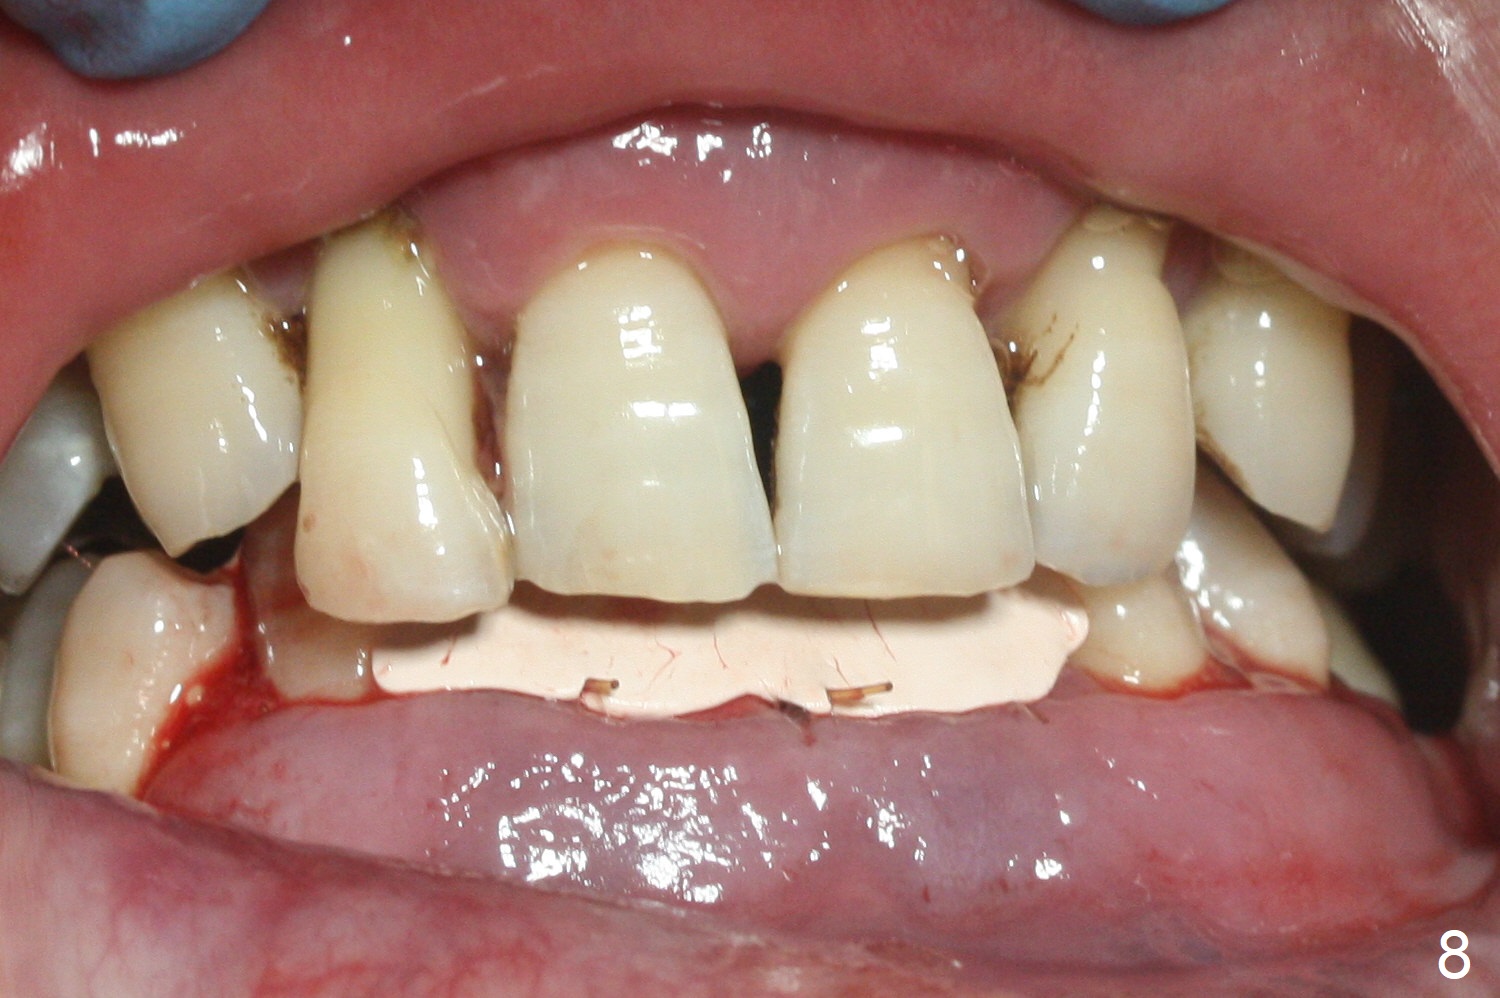

After extraction of 4 of the lower incisors, there are basically 2 sockets (#23/24 and 25/26), separated by the apparently midline bone (Fig.1 red line). In spite of using Lindamann bur to move the 25/26 osteotomy mesially, a 3x14(2) mm dummy implant remains close to the tooth #27 (Fig.2). The terminal branch of the Incisive Canal (<) is located between the lateral and central incisors. A de novo osteotomy (Fig.3 (1.5 mm drill)) is made mesial to the original one (O). While the 3x14(2) mm dummy implant is incompletely placed at #25/26, a 3x14(4) mm 1-piece one is placed at #23/24 (Fig.4). Finally the same implant is placed at #25/26 with placement of mineralized cortical/cancellous bone (Fig.5 *). When the large sockets are sutured, the supraerupted teeth #7-9 touch the lower gingiva (Fig.6). The incisal edge is reduced for clearance (Fig.7). Periodontal dressing is less likely to be dislodged with the incisal edge reduction (Fig.8,9). A provisional FPD is fabricated 1 week postop. Hard (Fig.10) and soft (Fig.11,12) tissues heal 5.5 months postop. The patient returns for crown cementation 3 months post impression (9 months postop, Fig.13,14).